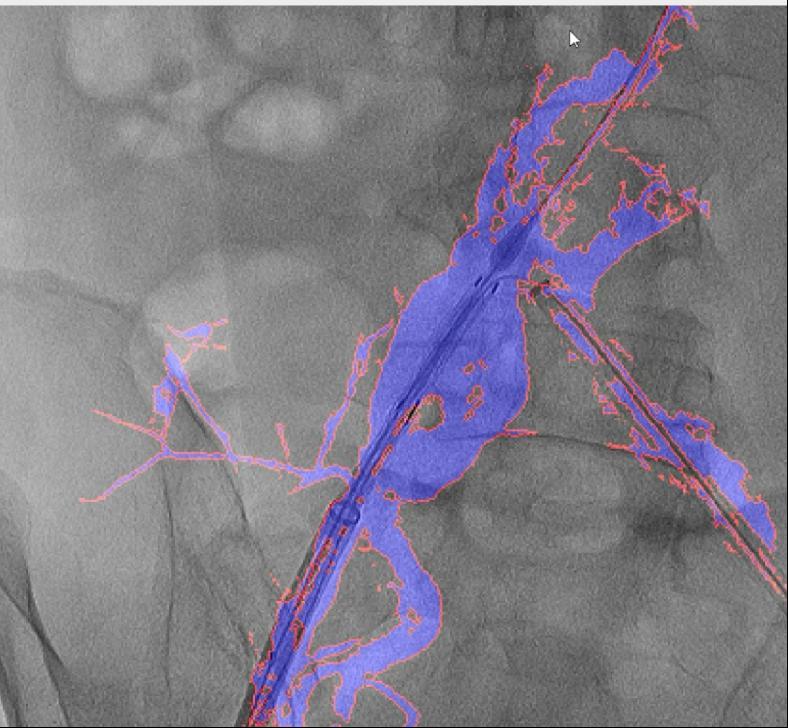

本研究案例使用10ml造影剂一次造影,实现EVAR术中髂内动脉重建,图中蓝色部分为造影显示的真实血管,红色边框为图像分割结果,融合图像的透明度可调节,与真实血管完全贴合,血管、器械的细节都清晰可见。

国外报道的DSA术中图像融合技术,融合图像模糊不清,CTA图像为3D重建影像,DSA为2D影像,两者图层之间简单重叠覆盖,清晰度明显受到相互影响。